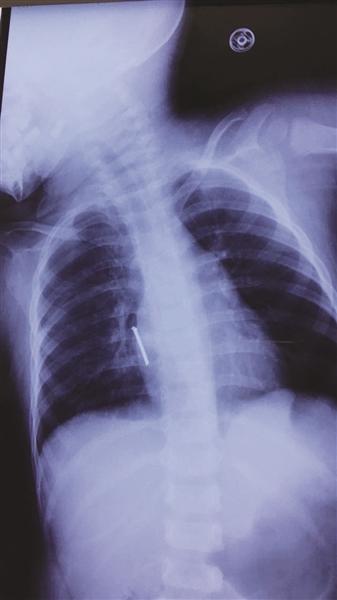

胸片显示,气钉扎进孩子胸腔,差一点就要了孩子的命。

一瞬间,一个长5厘米左右的钉子射进阳阳的心脏附近!据了解,气钉枪打出钉的力度很大,很有冲击力和杀伤力,速度一般60米/秒,厉害的可射穿1cm钢板。许先生看到此景,整个人都蒙了。带阳阳火速去医院,他在心里不停祈祷:“千万别刺到心脏!千万别……”

“从片子上看,钉子尖就靠近心脏。如果直接拔钉子,钉子穿透心脏的话,会引起大出血,继而危及生命,也可能胸腔内存有大量积血会填塞心脏,十分危险。”

在进行充分评估后,专家们决定手术打开胸腔,后发现钉子的钉尖已经穿入右心房肌层3毫米,已造成胸腔积血150毫升。“如果钉子再深入一点,那抢救都来不及了。”所幸手术顺利,阳阳脱离了生命危险。